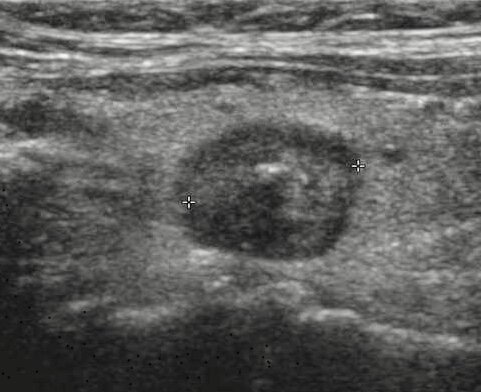

Узел щитовидной железы на УЗИ, размером более 1см: необходима биопсия.